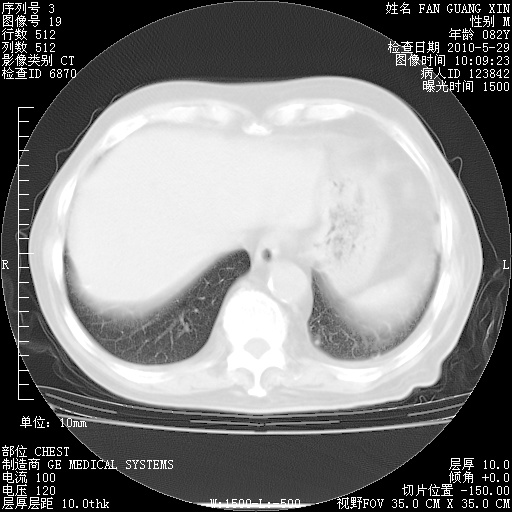

治疗3周后的肺部CT纵隔窗

从胸部影像学来看,的确有好转。至于目前为何发热不甚清楚?除了发热还有其他症状如有无喀痰,痰呈丝状吗?等等。尽量搜寻有无致发热其它可能原因?真菌?其它?如果的确无其他致发热的原因,考虑将甲强龙调至60-80mg bid/日。免疫全套基本无异常,考虑多系特发性肺间质纤维化